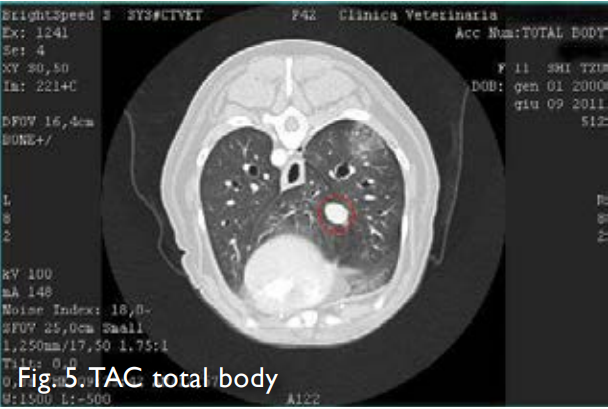

КЛИНИЧЕСКИЙ СЛУЧАЙ № 2 – МЕДЕЯ Терминальный пациент, страдающий папиллярной аденокарциномой бронхиальных канальцев. Прогноз жизни от 1 до 5 месяцев Последующее наблюдение 1 год 3 месяца и 14 дней. Уровень исцеления 2 Недавний анамнез Частый кашель и непонятная астения. Ультразвуковое исследование: Печень неоднородная из-за наличия неоднородной фокальной области. Почки с потерей кортико-медуллярной четкости и эхогенное поражение в правой части грудной клетки. Эхокардиография: митральные эндокардиозные разращения с пролапсом передней створки при отсутствии ремоделирования левого предсердия и желудочка. Класс сердечной недостаточности B1. Июнь 2011 КТ: подозрение на аденокарциному легкого правой каудальной доли, дифференциальный диагноз другая неоплазия, гранулема. Легкая гепатомегалия с мультифокальными поражениями печени с кистозным/геморрагическим компонентом, дифференциальный диагноз гепатит, стероидная гепатопатия и узловая гиперплазия, аденома, менее вероятны метастатические поражения. Билатеральная нефропатия с камнями, гиперплазия надпочечников (Кушинг, активация). Гистология легких: Бронхиальная тубулопапиллярная аденокарцинома. Гистология печени: Картина, совместимая с узловой гиперплазией, вакуольная дегенерация гепатоцитов. ПРОГНОЗ проф. Буракко: Университет Турина Время выживания От 1 до 5 месяцев со средним значением 3 14 июня 2011 Биохимический профиль: PT 6,1 (8-10). Фибриноген 484 (150-450).